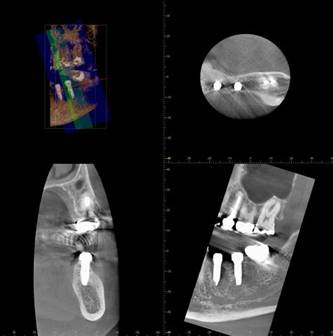

ブリッジの破折、下顎隆起が大きく義歯が不向きだったケース

小臼歯が破折し抜歯になりました。咬む力が強く長いブリッジは予後に不安がありました。また下顎隆起が大きく、部分義歯も不向きでした

そこでインプラントにしました

上部構造はフルジルコニア冠にしました

術後のCBCT

インプラントの重大な事故は下顎管から十分な距離をとれば防げます

インプラントにする前のパノラマレントゲン